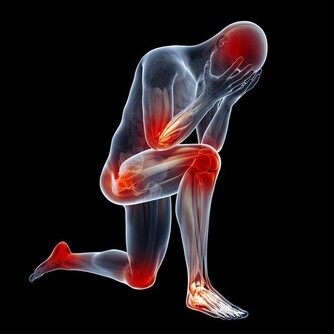

開頭我們就說了,來者大多是中年女性,這就不得不考慮性別和年齡兩個重要因素,我們自然而然會想到絕經和更年期。45-55之間的女性,逐漸發胖、衰老,體內的鈣質流失,關節負擔越來越重,出現了病理性改變,其實,不僅是手指,患者的膝蓋、肩膀、腰椎都可能受此影響。

五十歲上下的女性本身就容易生病,關於骨骼上的疾病非常常見,要有保養的意思才好,平時使用雙手要注意休息,同一個動作不宜長時間重複進行,總之記住6個字:保暖、補鈣、休息。